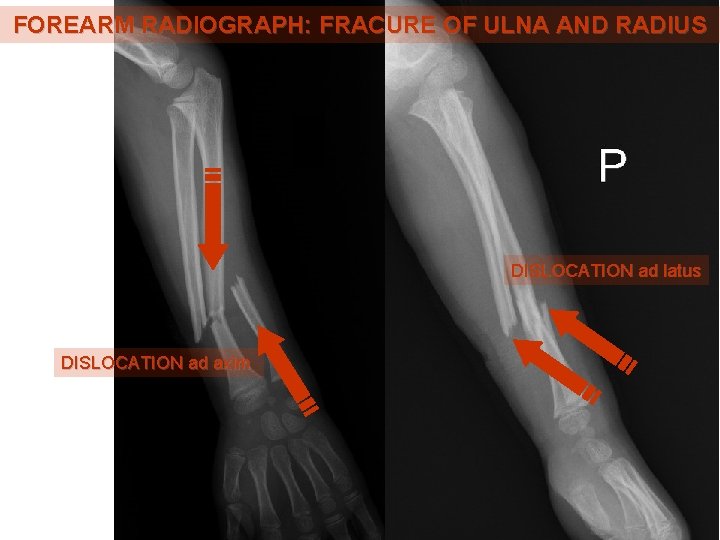

FOREARM RADIOGRAPH: FRACURE OF ULNA AND RADIUS DISLOCATION ad latus DISLOCATION ad axim